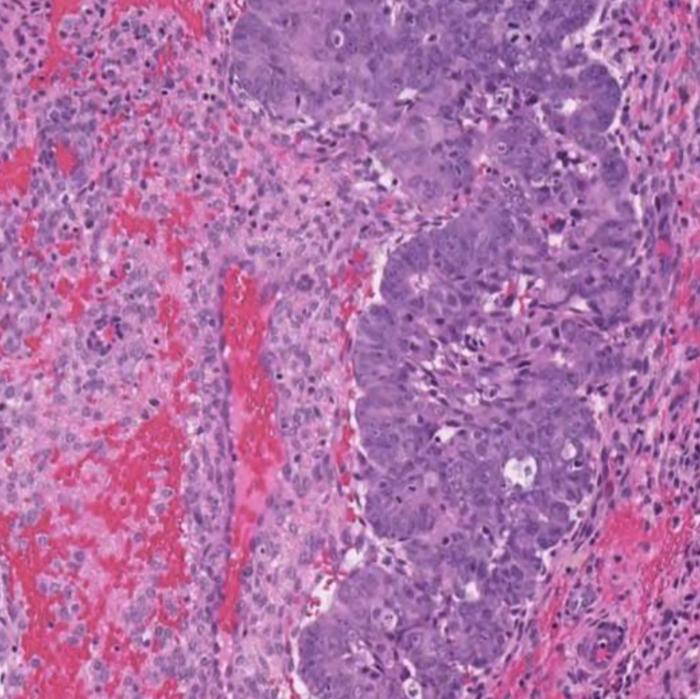

Dr. Bashashati and his team developed a deep learning AI model that analyzes images of tissue samples collected from patients. The AI was trained to differentiate between different subtypes, and after analyzing over 2,300 cancer tissue images, pinpointed the new subgroup that exhibited markedly inferior survival rates.

“The power of AI is that it can objectively look at large sets of images and identify patterns that elude human pathologists,” said Dr. Bashashati. “It’s finding the needle in the haystack. It tells us this group of cancers with these characteristics are the worst offenders and represent a higher risk for patients.”